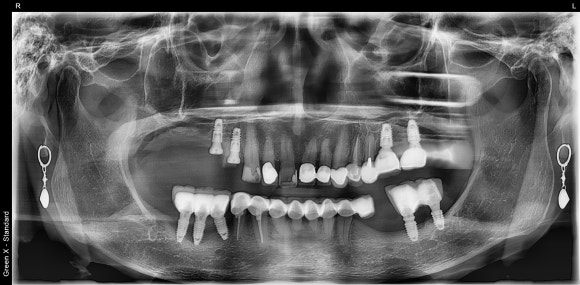

아래 사진은 기나긴 치과 여정 끝에 저를 만나셔서

오른쪽 위 임플란트를 진행 중이신 환자분이십니다.

하얗게 보이는 치아들이 크라운으로 씌운 치아인데요,

엑스레이만 봐서는 크라운 하방에 충치가 있는지 없는지 알 수가 없습니다.

다 멀쩡해보이는데요??